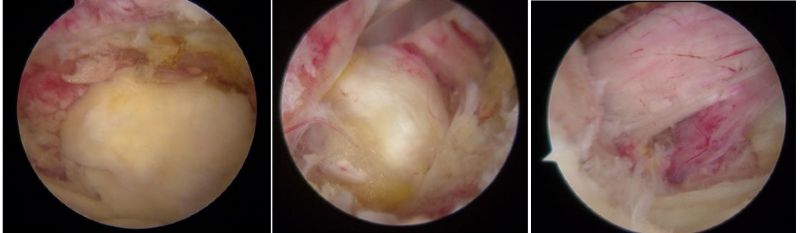

骨科內(nèi)鏡下的腰椎組織